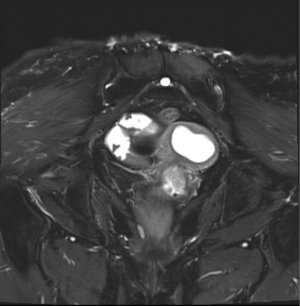

A 62-year-old female presented to gynecology out-patient department (OPD) in March 2025 with complaints of episodic bleeding per vaginum for 6 months (symptoms began around September 2024). It was insidious in onset, gradually progressive and associated with dull pelvic pain and foul-smelling discharge per vaginum. A history of occasional epigastric discomfort with significant weight loss was also elicited. No relevant medical, surgical, family, or personal history was noted. Pelvic examination revealed a 2 cm × 2 cm friable polypoidal growth over the cervical os without parametrial/rectal mucosal involvement. Magnetic resonance imaging (MRI) of the abdomen and pelvis demonstrated an ill-defined soft tissue lesion in the neck & body of pancreas measuring 3.2 cm × 4.2 cm × 3.2 cm, completely encasing the portal, splenic and superior mesenteric veins. Another soft tissue lesion of 2 cm × 2.2 cm × 3 cm was seen in cervical and lower uterine segment without any parametrial extension (Figure 1). Whole body positron emission tomography-computed tomography (PET-CT) scan showed high metabolic activity in the pancreatic and cervical lesions, with no other metabolically active focus elsewhere in the body (Figure 2). Serum carcinoembryonic antigen (CEA) was 22 ng/mL (normal: <3 ng/mL) and carbohydrate antigen 19-9 (CA19-9) was 1,532 U/mL (normal: <35 U/mL). Hemogram and other biochemistry parameters were within normal limits.Endoscopic ultrasound-guided fine needle aspiration cytology from pancreatic mass showed adenocarcinoma with mucinous differentiation (Figure 3). Punch biopsy from cervix was suggestive of adenocarcinoma.